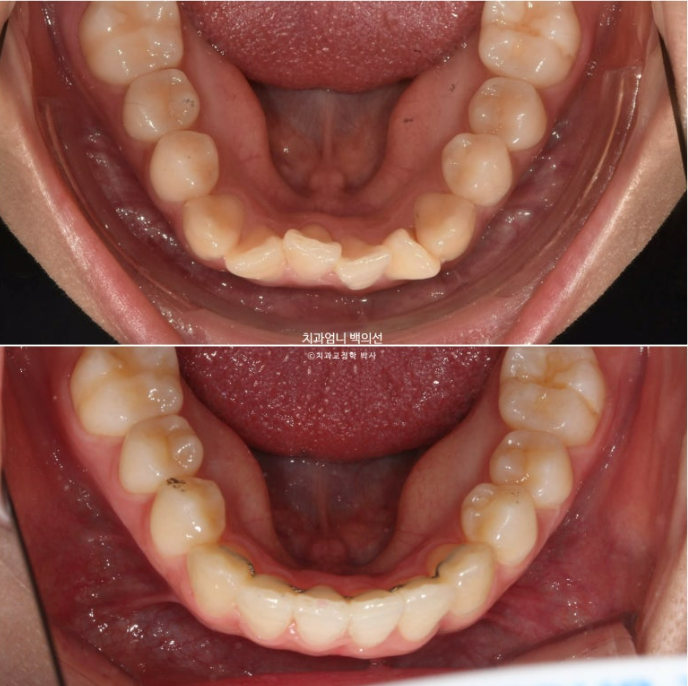

2023년 12월 앞니 부분교정을 원해서 내원한 분 입니다.

앞니 두 개가 크기도 하고 내려와 있습니다.

파란 화살표에 작은어금니 덧니도 보입니다.

아래 앞니가 많이 삐뚤 합니다.

어금니 교합이 그리 좋은 편은 아니었지만 환자분은 씹는데 불편함을 못 느끼는 상태였고 앞니 배열만 원하셨습니다.

23.12~24.09

고무줄 사용으로 송곳니 교합관계도 개선되었습니다.